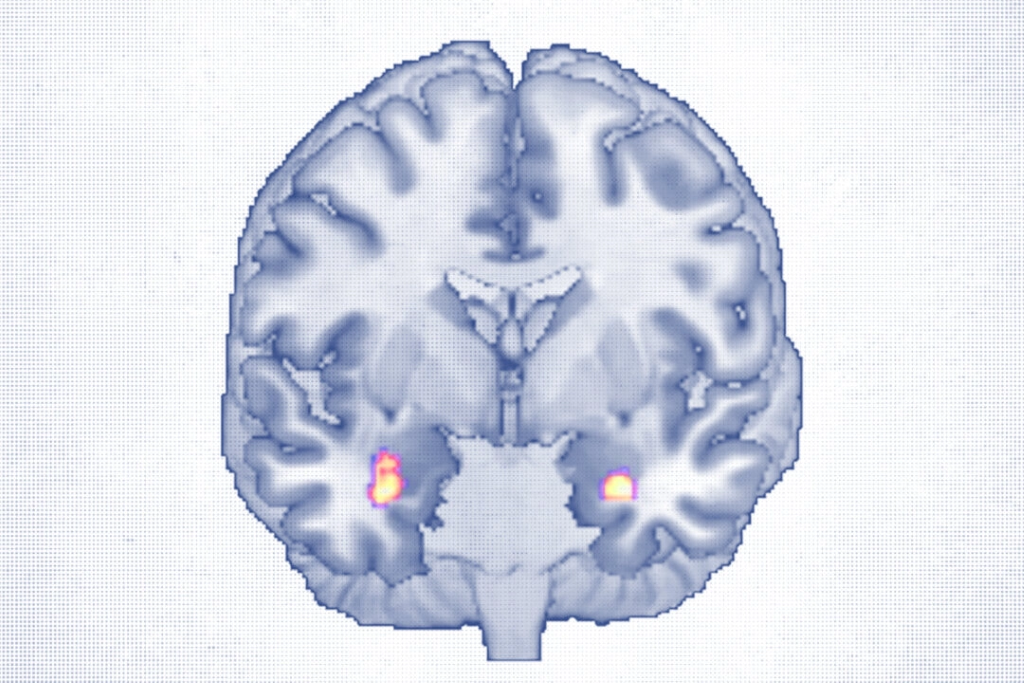

Štúdia sledovala 30 dospelých vo veku od 18 do 65 rokov s ťažkou depresívnou poruchou, ktorí počas 40 týždňov absolvovali približne 20 sedení KBT. Vysokokvalitné MRI snímky vyhotovené pred liečbou a po nej ukázali nárast objemu sivej hmoty v amygdale – oblasti, kde spracúvame emócie – a v prednom hipokampe, ktorý zodpovedá za pamäť a reguláciu nálady.

Obe oblasti sú známe tým, že sa u ľudí s depresiou zmenšujú, takže ich rast môže podľa vedcov naznačovať uzdravenie. Na konci štúdie 19 z 30 účastníkov už nespĺňalo klinické kritériá na to, aby im bola diagnostikovaná depresia. Zväčšenie objemu sivej hmoty v amygdale súviselo so zlepšenou schopnosťou vnímať emócie, najmä vlastné, uviedol Redlich.